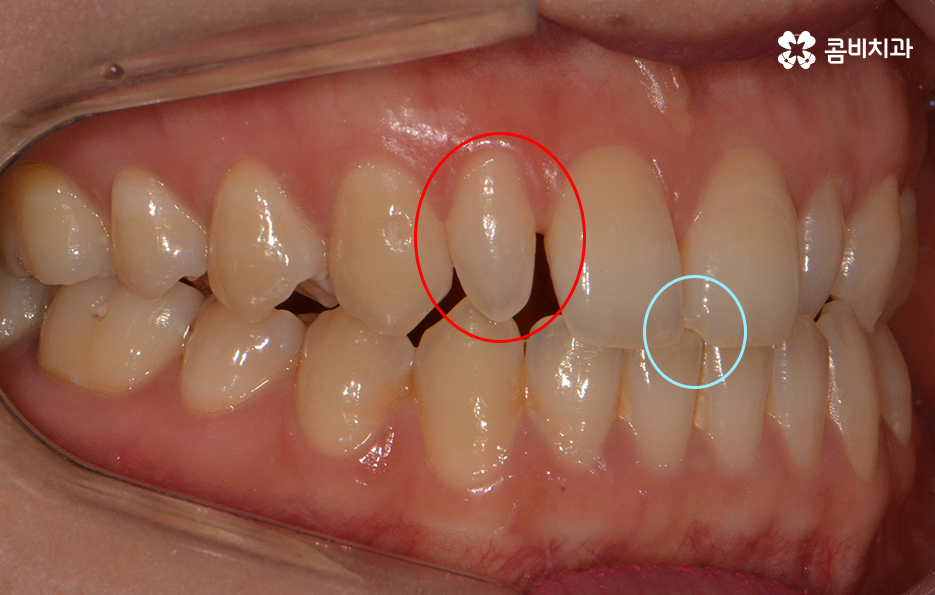

파란 원 - 치아의 깨짐, 빨간 원 - 왜소치

왜소치란? - 일반적인 치아에 비해 비정상적으로 작은 치아를 의미 합니다. 왜소치가 앞니 부분에 위치한 경우 치아가 벌어져 보이거나 심미적인 부담감을 느끼실 수 있습니다.

옆모습을 볼 때 치아 사이가 유독 벌어져 보이는데 심미적으로도

부담감을 느끼실 수 있지만 음식물이 치아 사이에 낀다거나

치아의 벌어짐으로 인해 치열이 반듯하게 자라지 못하기도 합니다.